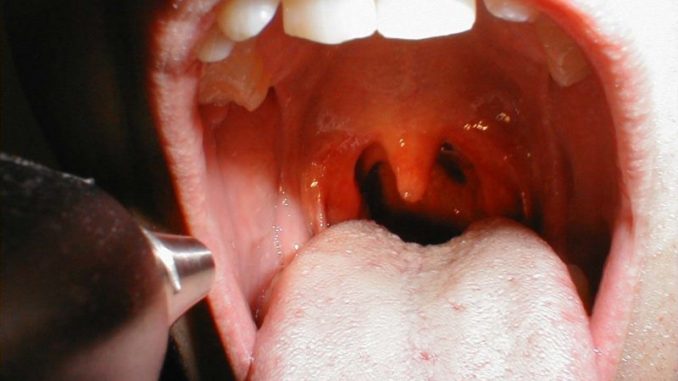

Этому трюку 400 лет и он доказал свою эффективность! В его эффективности сомневаются только те, кто не пробовал его применять! Мы применяем его всей семьёй уже много лет и он ни разу нас не подвёл! — Полезные советы